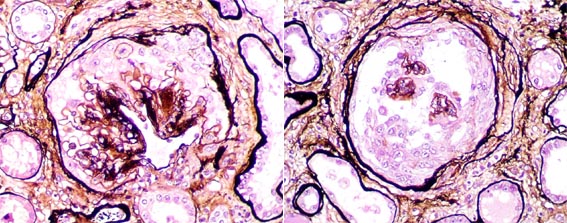

Figure 5.

Second post-transplantation biopsy. Left: Masson's trichrome stain, X400;

right: methenamine silver stain, X400.

Figure 6.

Second post-transplantation biopsy. Left and right: methenamine silver

stain, X400.